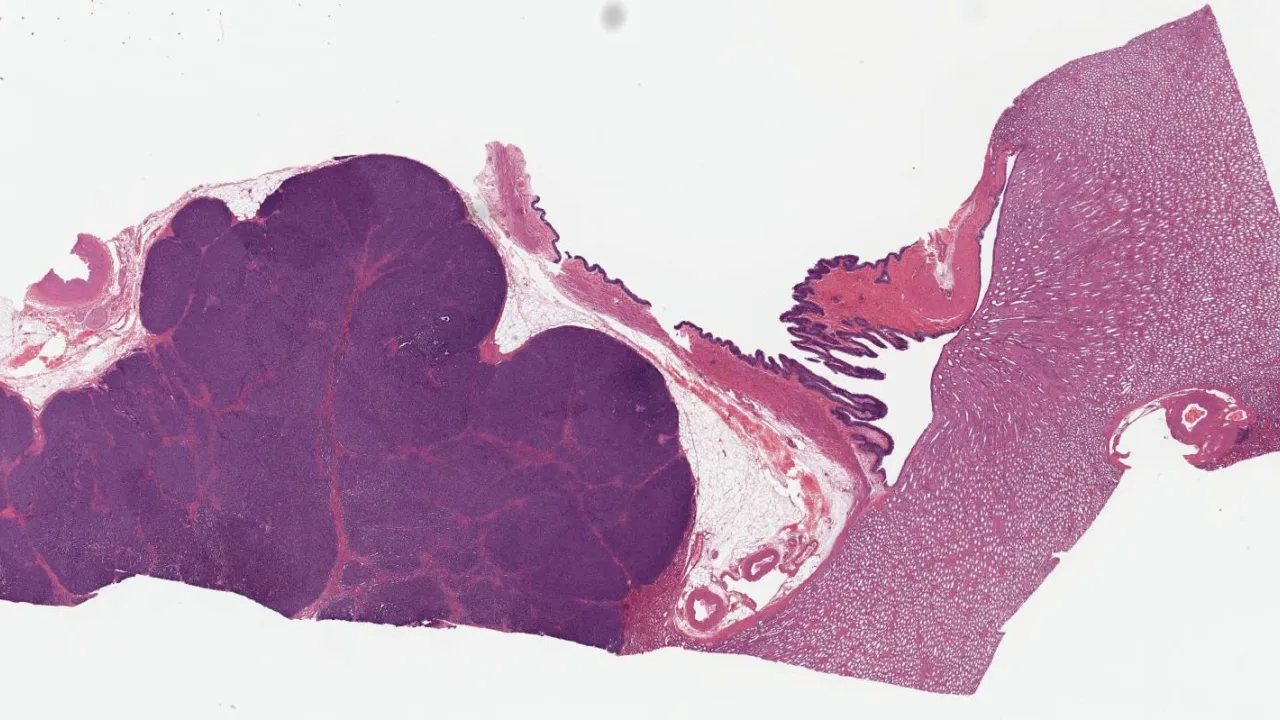

Breast, Fibroadenoma